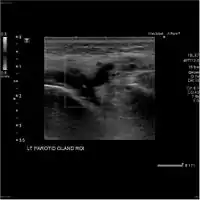

.jpg.webp) Acute left parotid sialadenitis Acute left parotid sialadenitis